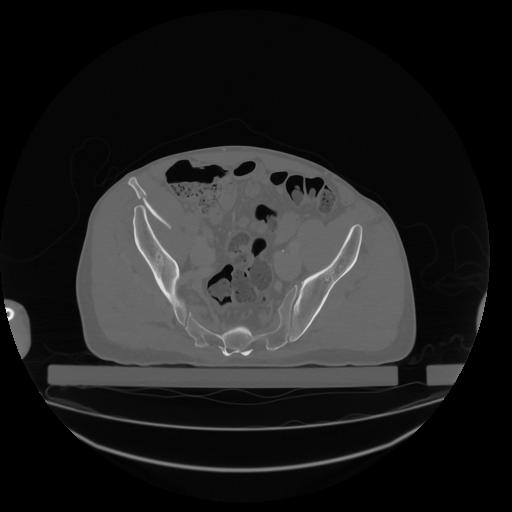

34 CUERPO,CE,Vol,1.0,CUERPO,,